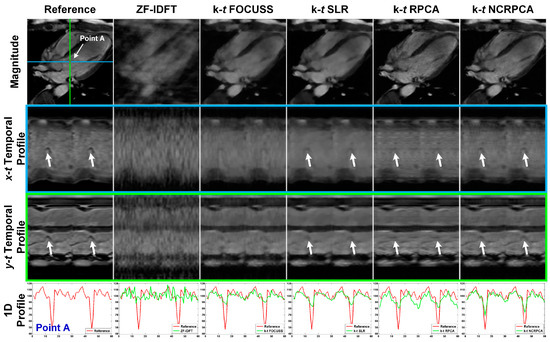

4.3. Comparisons on In Vivo Axial Cardiac Dataset

4.4. Comparisons on In Vivo Coronal Cardiac Dataset